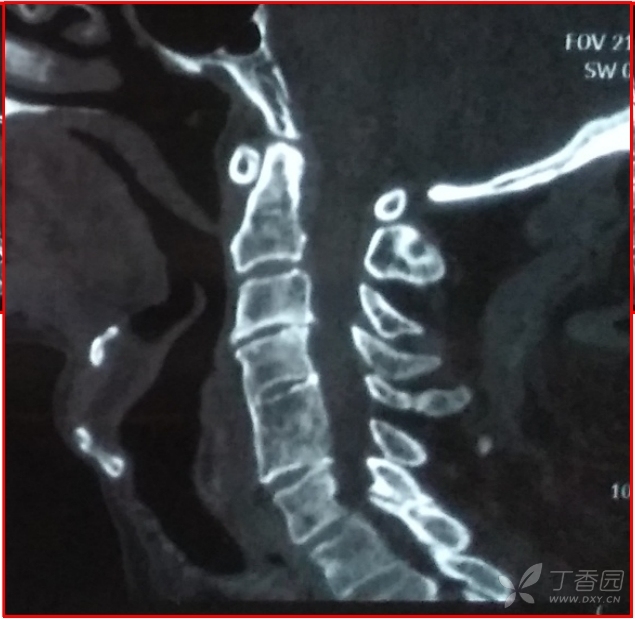

“骨头”挡了神经?一招“移山”解除警报!近日,潍坊市中医院脊柱骨一科成功为一名罹患脊髓型颈椎病伴颈椎后纵韧带骨化症(OPLL)的患者实施了颈椎前路椎体骨化物复合体前移术(ACAF),术后患者症状显著改善,四肢无力及双上肢麻木感明显减轻。 该患者因双上肢麻木、四肢无力就诊于潍坊市中医院脊柱骨一科,经检查确诊为...